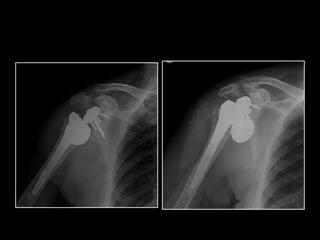

DESIGNS

SURGICAL TECHNIQUE

MADRID